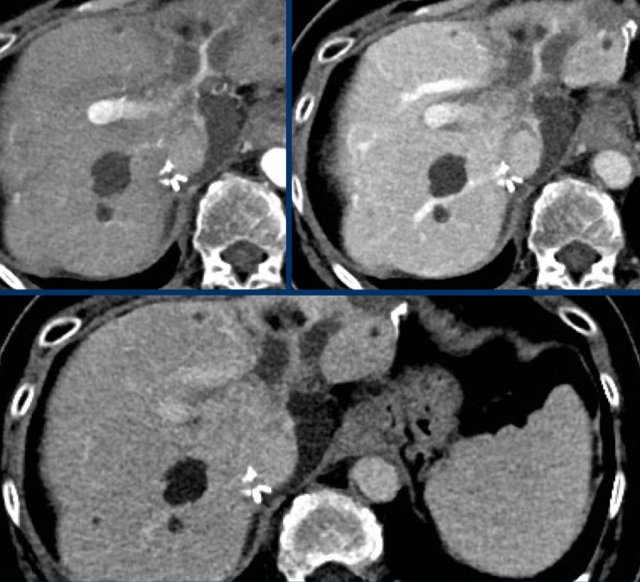

The images show an observation in segment 5 of the liver demonstrating arterial hyperenhancement.

The lesion has grown from 8 mm to 21 mm in 3 months, which means that there is threshold growth.